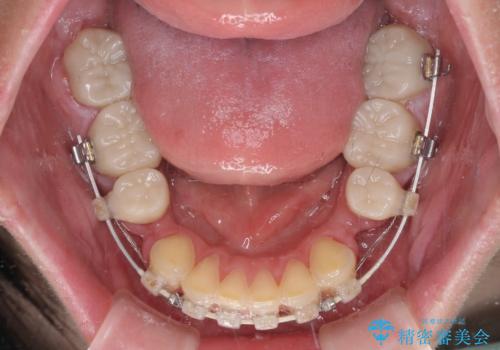

当初はほとんどの歯をむし歯治療のようにオールセラミッククラウンにて補綴治療を行う予定でしたが、仮歯に置き換えた時点で、口元の突出感や下顎前歯の叢生が気になるとのことで、上下左右の第一小臼歯4本を抜歯したワイヤー装置での抜歯矯正を行うこととしました。

矯正治療終了後に、残った歯をオールセラミッククラウンにて補綴治療を行うこととしました。